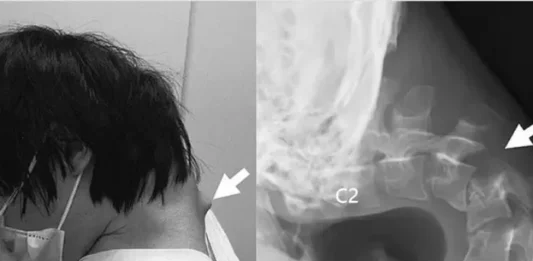

Problemas na Coluna: O Alerta Chocante de um Jovem com Síndrome da Cabeça Caída